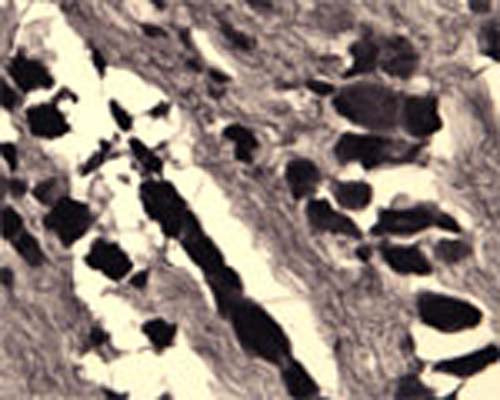

Our Anti-Sortilin rabbit polyclonal primary antibody detects human, mouse, and rat Sortilin, and is whole serum. It is validated for use in ELISA, IHC-Frozen.

IHC: 1:1000

Specificity was demonstrated by immunohistochemistry. Reacts with human, rat and mouse Sortilin. Other species not yet tested.